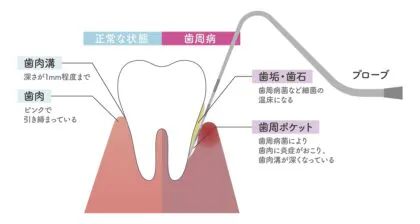

歯周病の進行

歯肉炎

歯肉炎は、歯肉のみが炎症を起こしており、歯根膜や歯槽骨はまだ破壊されていない状態です。歯ぐきが暗赤色で腫れ、歯磨きや食事時に出血しやすくなります。

軽度歯周病

軽度歯周病では、歯槽骨が歯根の長さの3分の1まで消失しています。歯ぐきの炎症が進行し、歯周ポケットができ、歯槽骨が溶け始めます。

中度歯周病

中度歯周病では、歯槽骨が歯根の長さの3分の1~2分の1まで消失しています。炎症が悪化し、歯根部が露出し、歯に冷たいものや熱いものがしみます。歯石が付着し、口臭もひどくなります。

重度歯周病

重度歯周病では、歯槽骨の大きな破壊が見られ、歯根はほとんど支えられず、歯が大きく動揺します。

食事が難しくなり、歯を抜く必要が生じ、入れ歯やインプラント治療も難しくなります。当院では、歯周外科治療や歯周組織再生療法などを行い、なるべく歯を残す治療を行います。